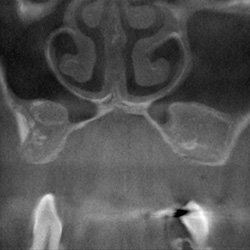

Chronisch polypöse Pansinusitis linksMukozele im linken Siebbein

mit Unterbrechung der Frontobasis

Z.n. Pansinus-Operation